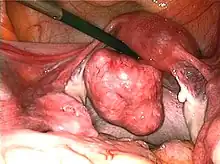

![]() | |

| Uterine fibroids as seen during laparoscopic surgery | |